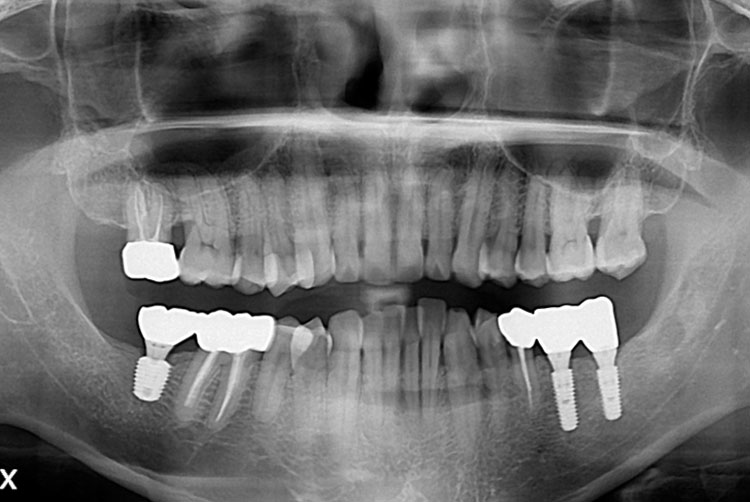

[임플란트] 임플란트

치료전 : 2017-06-15

세종치과는 많은 환자와 다양한 케이스를 바탕으로 항상 편안한 임플란트 수술을 제공하고자 노력하고,

오래동안 튼튼히 쓸 수 있는 임플란트 수술을 가장 큰 목표로 삼고 있습니다.